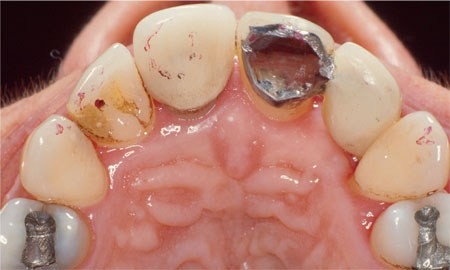

While some occlusal problems occur naturally many are iatrogenic. These often occur while providing restorations or carrying out occlusal adjustment and splint treatment. They result simply from a failure to ensure adequate occlusal harmony and occlusal stability.

To avoid occlusal pitfalls with restorations means going back to basics, being self-critical about your dentistry and not just blaming the technician. Remember a high crown is the end result of a chain of procedures involving occlusal examination, tooth preparation, impressions, jaw registration and cast mounting. Any one of these may incorporate an error including the humble alginate impression used to record the opposing arch.

Dentists may precipitate a variety of biomechanical problems with anterior restorations which interfere with anterior guidance. To ensure a predictable outcome it is important either to conserve anterior guidance or reorganise it in a controlled and predictable way. For work involving more than just a couple of indirect restorations access to a facebow and a lab which uses a semi-adjustable articulator is invaluable.